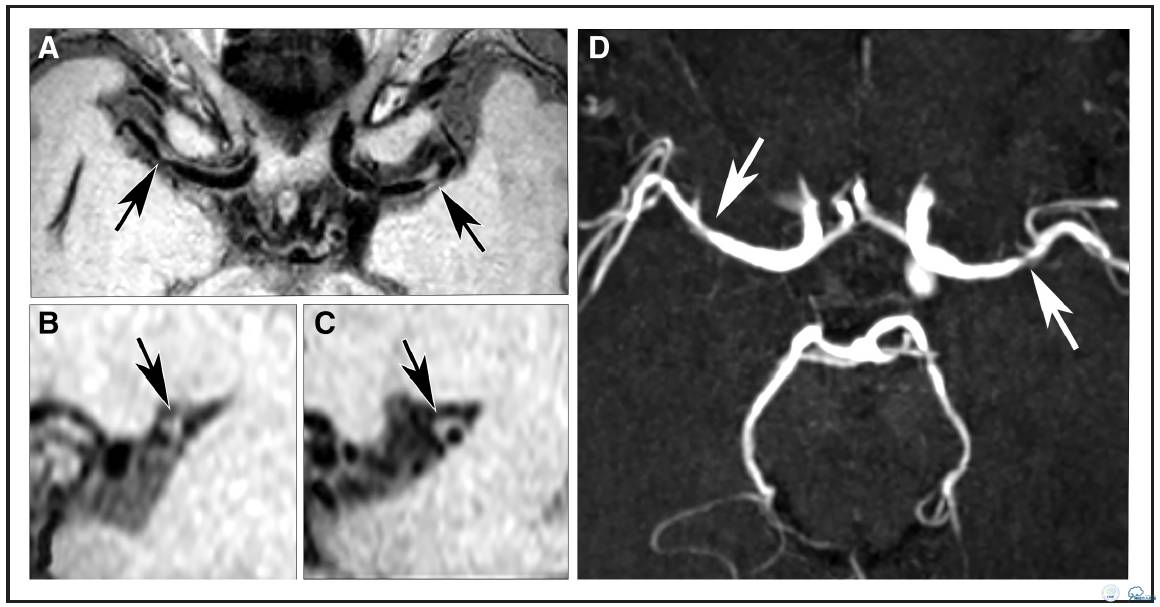

图2:78岁TIA女性患者。A:等中心重建容积采集T1加权快速自旋回波序列成像发现右侧大脑中动脉双侧局部血管壁病变(箭头A),矢状位重建图像(B)右侧大脑中动脉病变(C)显示双侧病变均为偏心性。D:横断面时间飞跃法磁共振血管造影显示对应位置症状性左侧MCA狭窄,无症状性右侧MCA不规则狭窄(箭头D)。